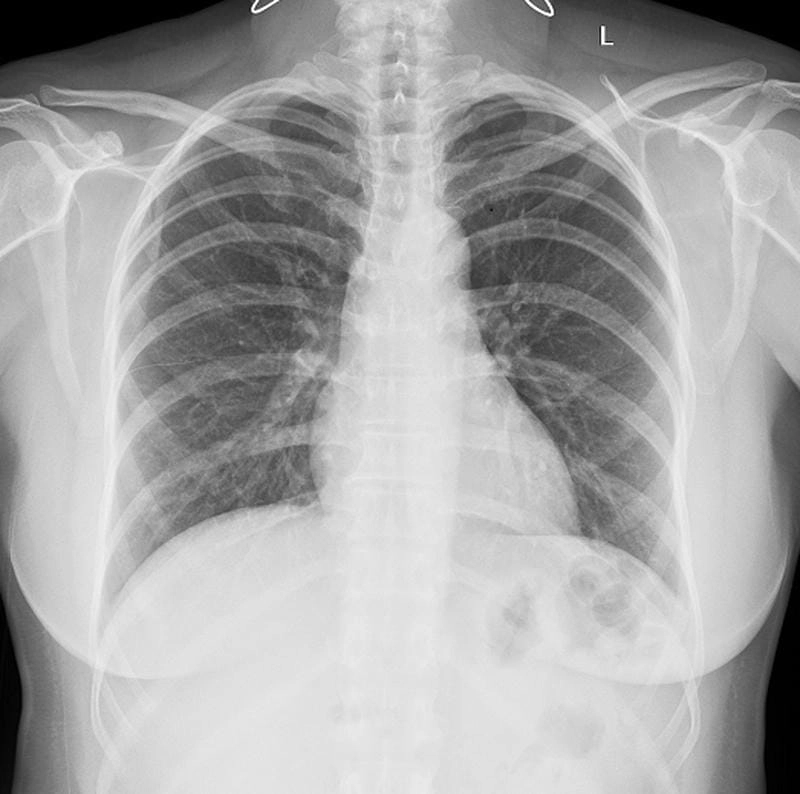

Bạn sẽ phải rùng mình khi chiêm ngưỡng hình ảnh bệnh lao phổi là như thế nào dưới ống kính y học thực tế. Những bức ảnh chụp X-quang cho thấy phổi bị tổn thương nặng, xuất hiện những đốm trắng mờ như bóng ma ám ảnh. Không chỉ là các tổn thương vật lý, đây còn là những “chứng tích sống” của căn bệnh âm thầm hủy hoại cơ thể qua từng hơi thở. Từ viêm nhẹ đến tổn thương lan rộng, hình ảnh bệnh lao phổi khiến người xem không thể rời mắt vì mức độ nghiêm trọng mà nó thể hiện rõ ràng qua từng chi tiết.

Cảnh báo: tổng hợp ảnh bệnh lao phổi chân thực này không dành cho người yếu tim. Đây là loạt hình ảnh y khoa được các chuyên gia sưu tầm và xác thực, ghi lại quá trình tiến triển của bệnh từ giai đoạn đầu đến giai đoạn nguy kịch. Từng mảng mô phổi bị ăn mòn, xơ hóa, hoại tử được phơi bày rõ nét dưới ánh sáng X-quang lạnh lùng. Những hình ảnh này không chỉ mang tính chất minh họa y học, mà còn là hồi chuông cảnh tỉnh cho bất kỳ ai còn lơ là với căn bệnh nguy hiểm này.